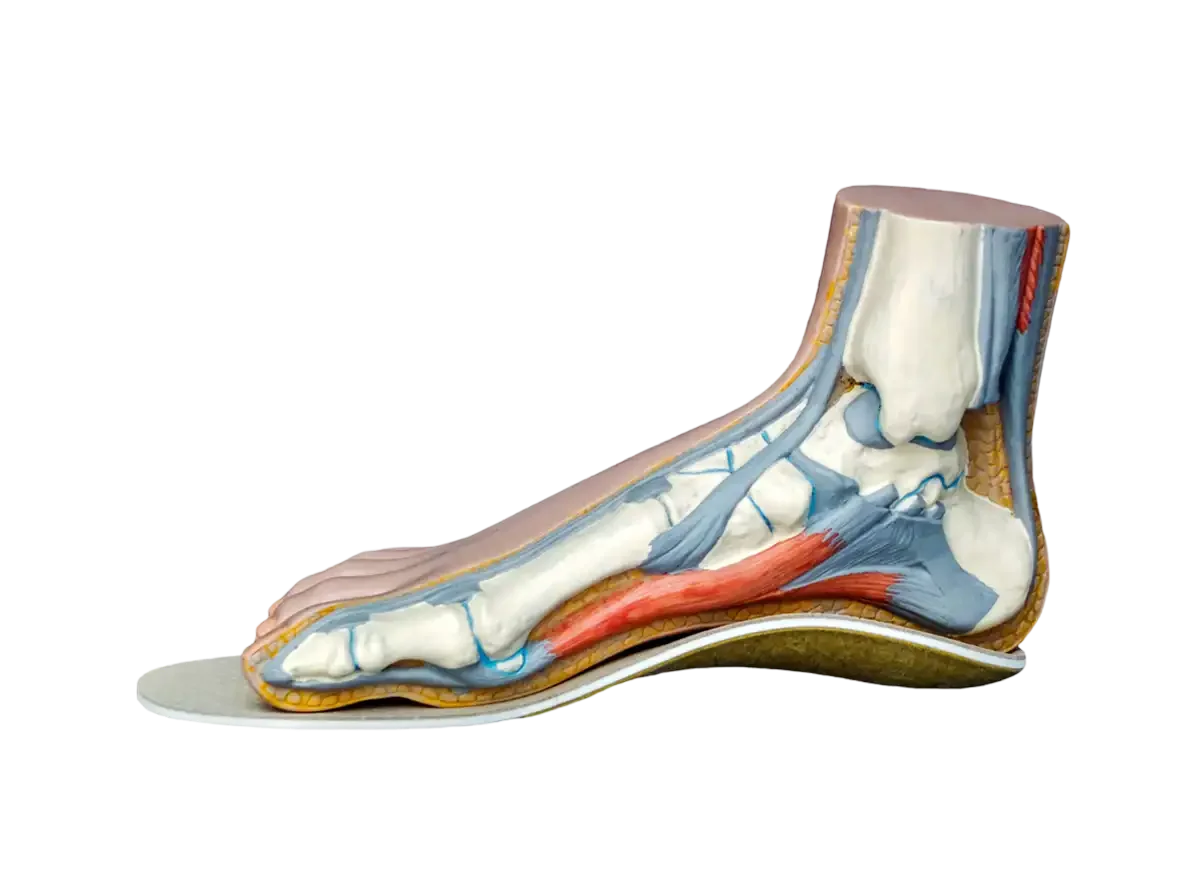

Las plantillas podológicas son, probablemente, uno de los tratamientos más conocidos dentro de la podología…...